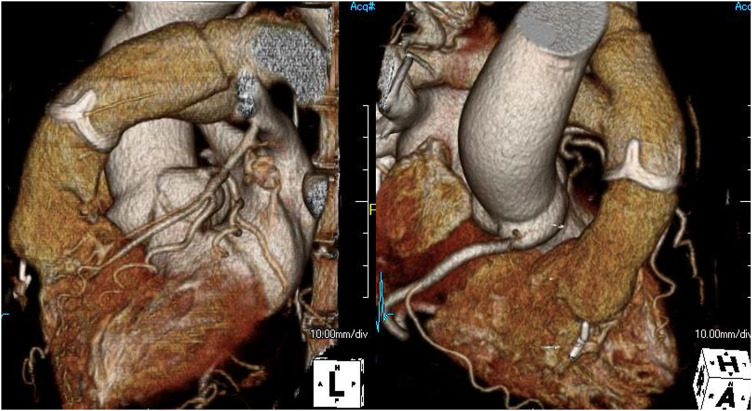

Case presentation: A 64-year-old woman, complaining of dyspnea for a month, was referred for a pulmonary artery tumor. Imaging studies confirmed an intraluminal tumor that obstructs the pulmonary artery trunk and extends to the right ventricular wall and interventricular septum, suspecting a malignancy. During preoperative workups, she developed acute hemodynamic and respiratory deterioration due to pulmonary embolization, so emergency surgery was planned on a salvage basis. The tumor originated from the pulmonary artery intima just distal to the pulmonary valve, obstructed the pulmonary artery trunk, and extensively involved the left main coronary artery and the interventricular septum, where complete resection of the tumor was not achieved. Reconstruction of the pulmonary valve, the right ventricular outflow tract (RVOT), and bilateral pulmonary arteries were performed using a composite of a prosthetic valve and vascular grafts. The patient's postoperative course was uneventful, and she was discharged home asymptomatic. Pathological diagnosis of the operative specimen confirmed pulmonary intimal sarcoma. After 4 months of postoperative chemotherapy, tumor progression was confirmed. The patient passed away at home 8 months after surgery.